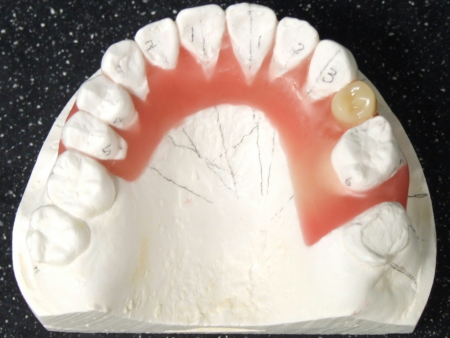

したがって右下前歯を動かさない計画のもと右下前歯の位置を基準としてそれ以外の歯を並べ直して理想的な歯並び、噛み合わせを再現した「セットアップ模型」を製作しました。

セットアップ模型:患者様の歯型をもとに作製した模型の歯の部分を切りだしてバラバラにしてから理想的な位置に並べ直して、咬合治療のゴールをシミュレーションし、確認するために用います。

このセットアップ模型を計測することでインプラントを埋入しなければならない正しい位置を知ることができます。

☆今回は右下前歯の位置を動かさない計画でしたので、治療前の右下前歯の位置を基準にインプラント埋入位置を決定しました。もし下顎の前歯を後方に移動したり、正中を変更したりする計画の場合にはこの移動量を加味してインプラント埋入位置を算定する必要があります。